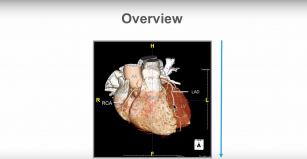

Identify normal heart structures on a cardiac CT scan. 19th Dec 2017 - Ronak Rajani, MD, FESC, FRCP, FSCCT Identify normal variants of various heart structures on a cardiac CT scan.